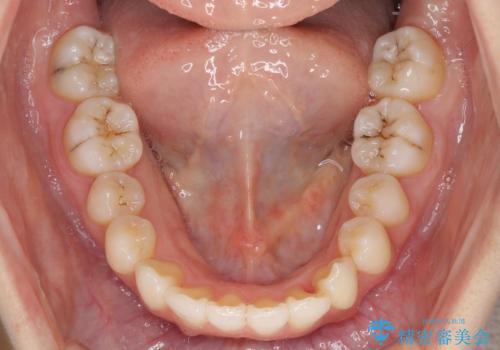

- 前歯のデコボコを気にして来院された患者様です。

叢生と捻転が随所に認められるものの、マウスピースで十分対応可能であったため、インビザラインにて矯正治療を行うこととしました。